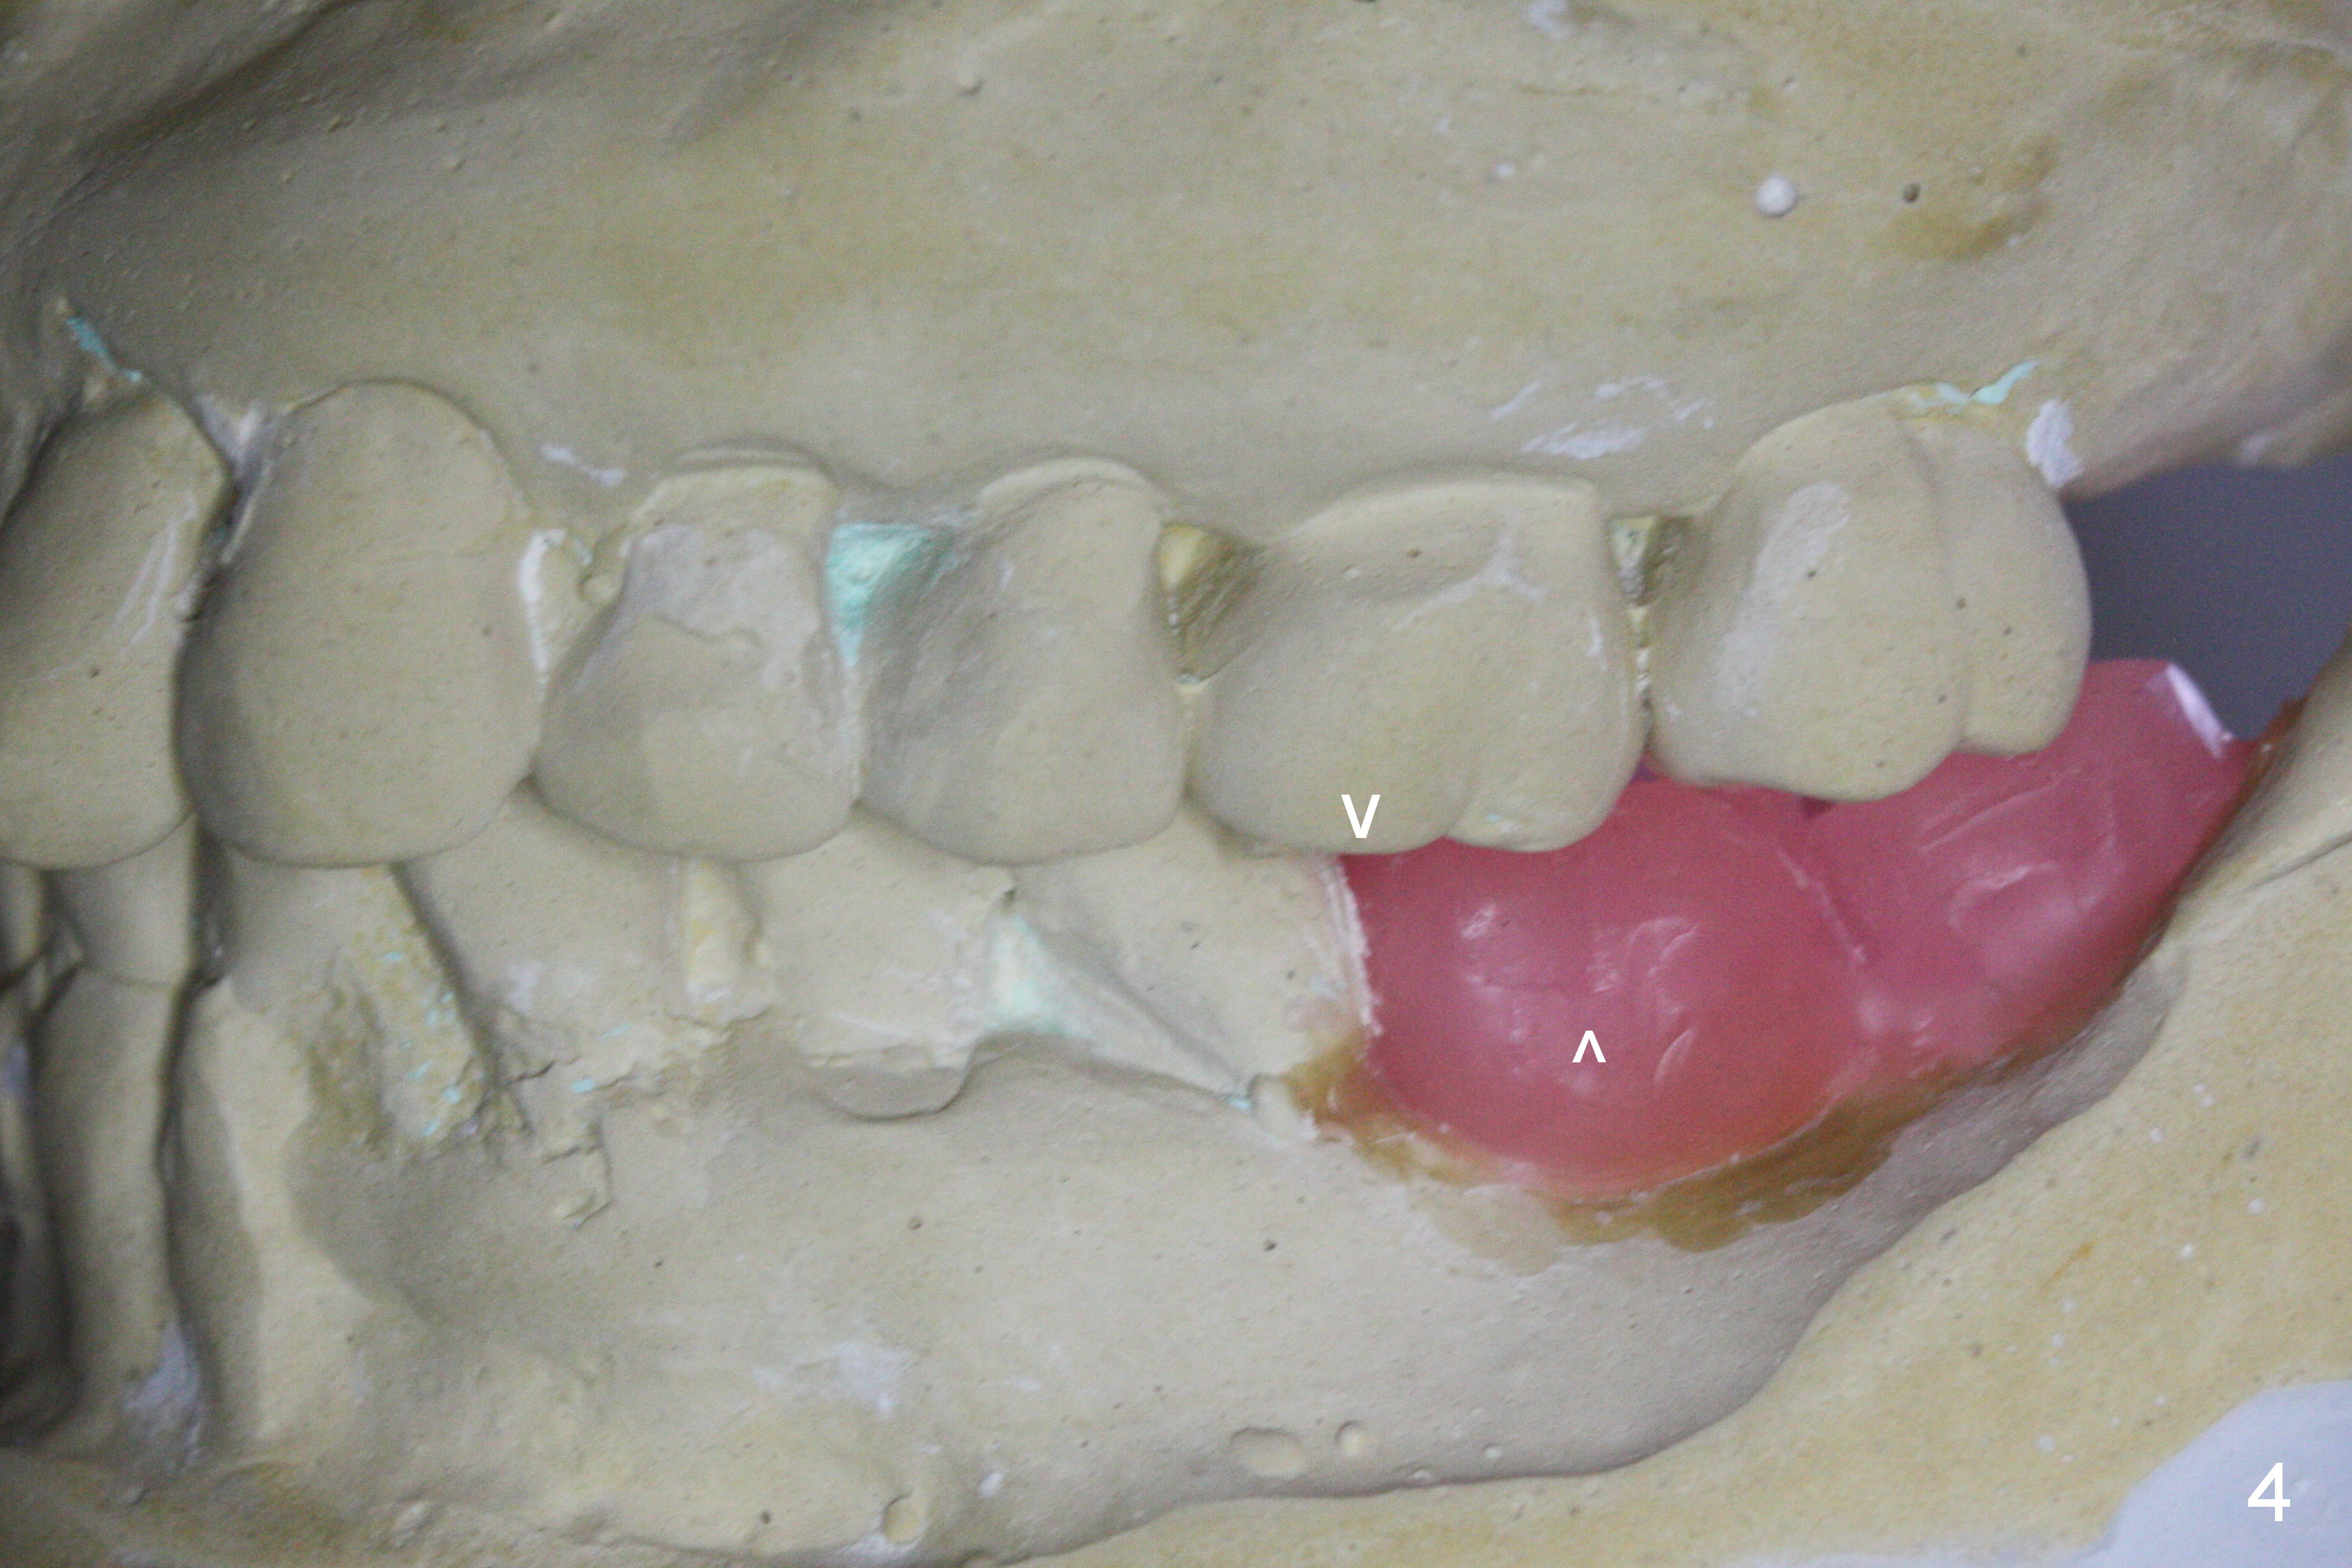

A 73-year-old woman requests implant restoration at #18 and 19 (Fig.1). The left posterior occlusion is Class II (Fig.1,2). The right one is Class I because of small dimension of the restoration at #30 (Fig.3 (premolar)). The normal size of the lower left molars will keep Class II occlusion (Fig.4), which may create cheek bite posteriorly. To correct the occlusion to Class I, move osteotomies to the mesial aspect of waxed-up molars (Fig.6 white circles). Finally a premolar crown and the 1st molar will be placed at #19 and 18, respectively. The supraerupted opposing molars (Fig.5 arrowheads) will to be adjusted when the abutments are placed at the lower molars.

A new setup of wax up is established immediately preop (Fig.10) to have atypical Class I occlusion between the upper 2nd molar and the lower 1st one (Fig.11 straight lines). Take photos of the occlusion post cementation.